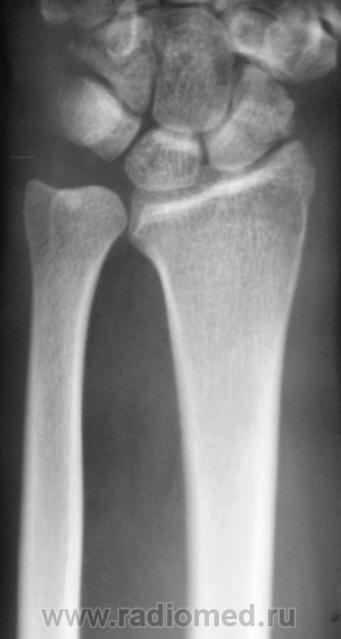

Катенёв Валенти... Дата публикации 15.10.2009, 20:32 Травма неделю тому. Пациент направлен на рентгенологическое исследование лучезапястного сустава с диагнозом "Перелом". Произведено исследование. Ваше мнение коллеги? Чт, 15/10/2009 - 20:36 #1 В.Б. Серов Не на сайте Был на сайте: 3 недели 3 дня назад Зарегистрирован: 16.07.2008 - 10:15 Публикации: 1376 Нужен косой снимок, подтвердить/опровергнуть перелом ладьи. Зри в корень! Чт, 15/10/2009 - 21:37 #2 Наталия Не на сайте Был на сайте: 9 лет 2 недели назад Зарегистрирован: 30.07.2008 - 13:24 Публикации: 538 Перелом ладьевидной кости без смещения виден хорошо. Чт, 15/10/2009 - 21:53 #3 Катенёв Валенти... Не на сайте Был на сайте: 7 лет 5 месяцев назад Зарегистрирован: 22.03.2008 - 22:15 Публикации: 54876 Да. линия перелома в ладьевидной кости, весьма хорошо дифференцируется

Перелом ладьевидной кости без смещения виден хорошо.

Да. линия перелома в ладьевидной кости, весьма хорошо дифференцируется